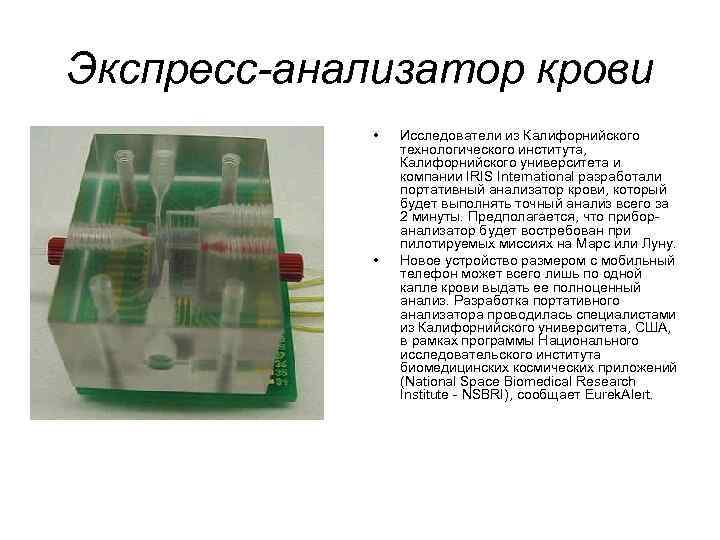

Экспресс-анализатор крови • • Исследователи из Калифорнийского технологического института, Калифорнийского университета и компании IRIS International разработали портативный анализатор крови, который будет выполнять точный анализ всего за 2 минуты. Предполагается, что приборанализатор будет востребован при пилотируемых миссиях на Марс или Луну. Новое устройство размером с мобильный телефон может всего лишь по одной капле крови выдать ее полноценный анализ. Разработка портативного анализатора проводилась специалистами из Калифорнийского университета, США, в рамках программы Национального исследовательского института биомедицинских космических приложений (National Space Biomedical Research Institute - NSBRI), сообщает Eurek. Alert.

Экспресс-анализатор крови • • Исследователи из Калифорнийского технологического института, Калифорнийского университета и компании IRIS International разработали портативный анализатор крови, который будет выполнять точный анализ всего за 2 минуты. Предполагается, что приборанализатор будет востребован при пилотируемых миссиях на Марс или Луну. Новое устройство размером с мобильный телефон может всего лишь по одной капле крови выдать ее полноценный анализ. Разработка портативного анализатора проводилась специалистами из Калифорнийского университета, США, в рамках программы Национального исследовательского института биомедицинских космических приложений (National Space Biomedical Research Institute - NSBRI), сообщает Eurek. Alert.